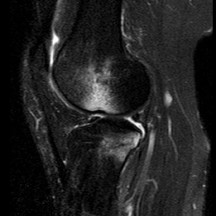

Question 1:

A 45-year-old recreational athlete presents with acute medial knee pain after feeling a 'pop' while deep squatting. MRI demonstrates an extrusion of the medial meniscus of 4 mm and a complete radial tear at the posterior root. Which of the following best describes the primary biomechanical consequence of this specific injury pattern?

Correct Answer: Loss of hoop stresses leading to peak contact pressures equivalent to a total meniscectomy

A posterior medial meniscus root tear disrupts the circumferential hoop stresses that the intact meniscus relies on to dissipate axial loads. Biomechanical studies demonstrate that a posterior root tear is functionally equivalent to a total meniscectomy in terms of decreasing contact area and dramatically increasing peak tibiofemoral contact pressures, leading to rapid chondrolysis and osteoarthritis if left untreated.